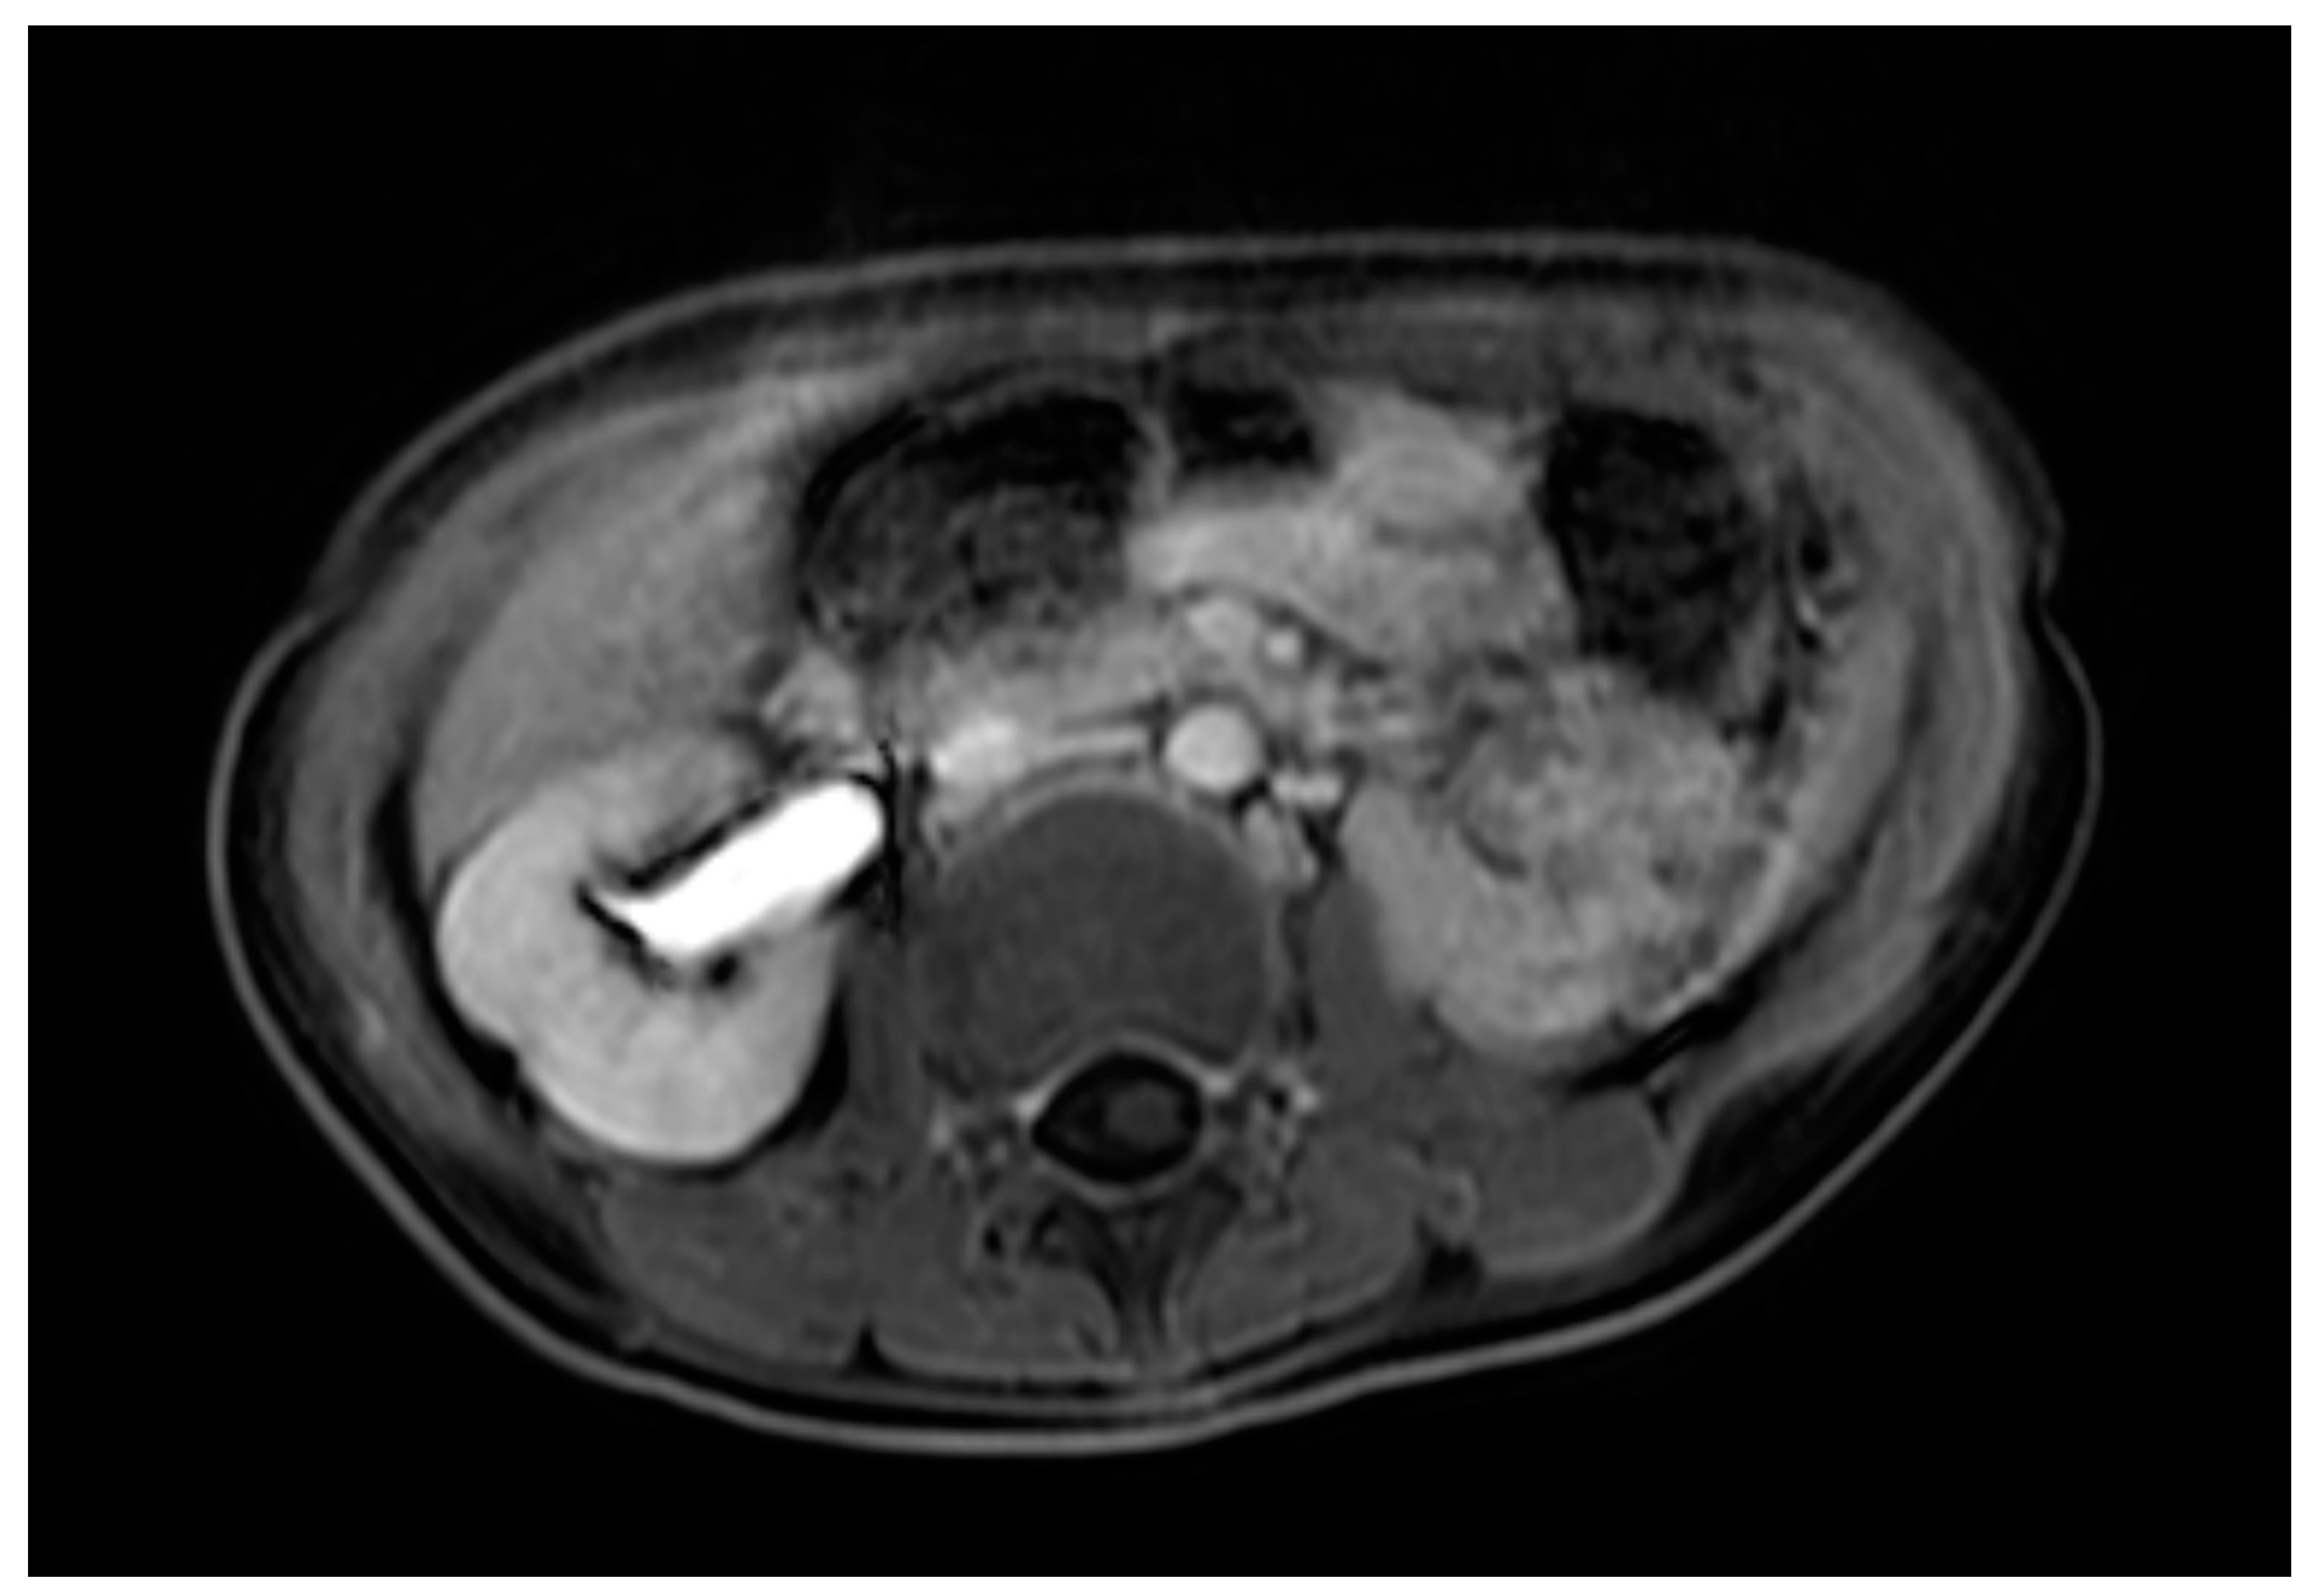

Case 1 was born at 36 weeks of gestation. An 8 cm cystic mass in the lower abdomen was detected on antenatal ultrasound from 32 weeks of gestation. The patient presented with a bulging mass over the vulva area. Magnetic resonance imaging (MRI) (Figure 1) showed a 9.1 cm cystic mass in the pelvic cavity, which extended to the vaginal orifice and caused left hydroureter, suggesting an imperforated hymen. Hymenotomy with a cross excision was performed, and 50 mL of milky fluids was drained. The patient is now 4 years, 4 months old, healthy without other medical issues.

Figure 1.

MRI of case 1: hydrometrocolpos manifested as an intraabdominal huge cystic mass.